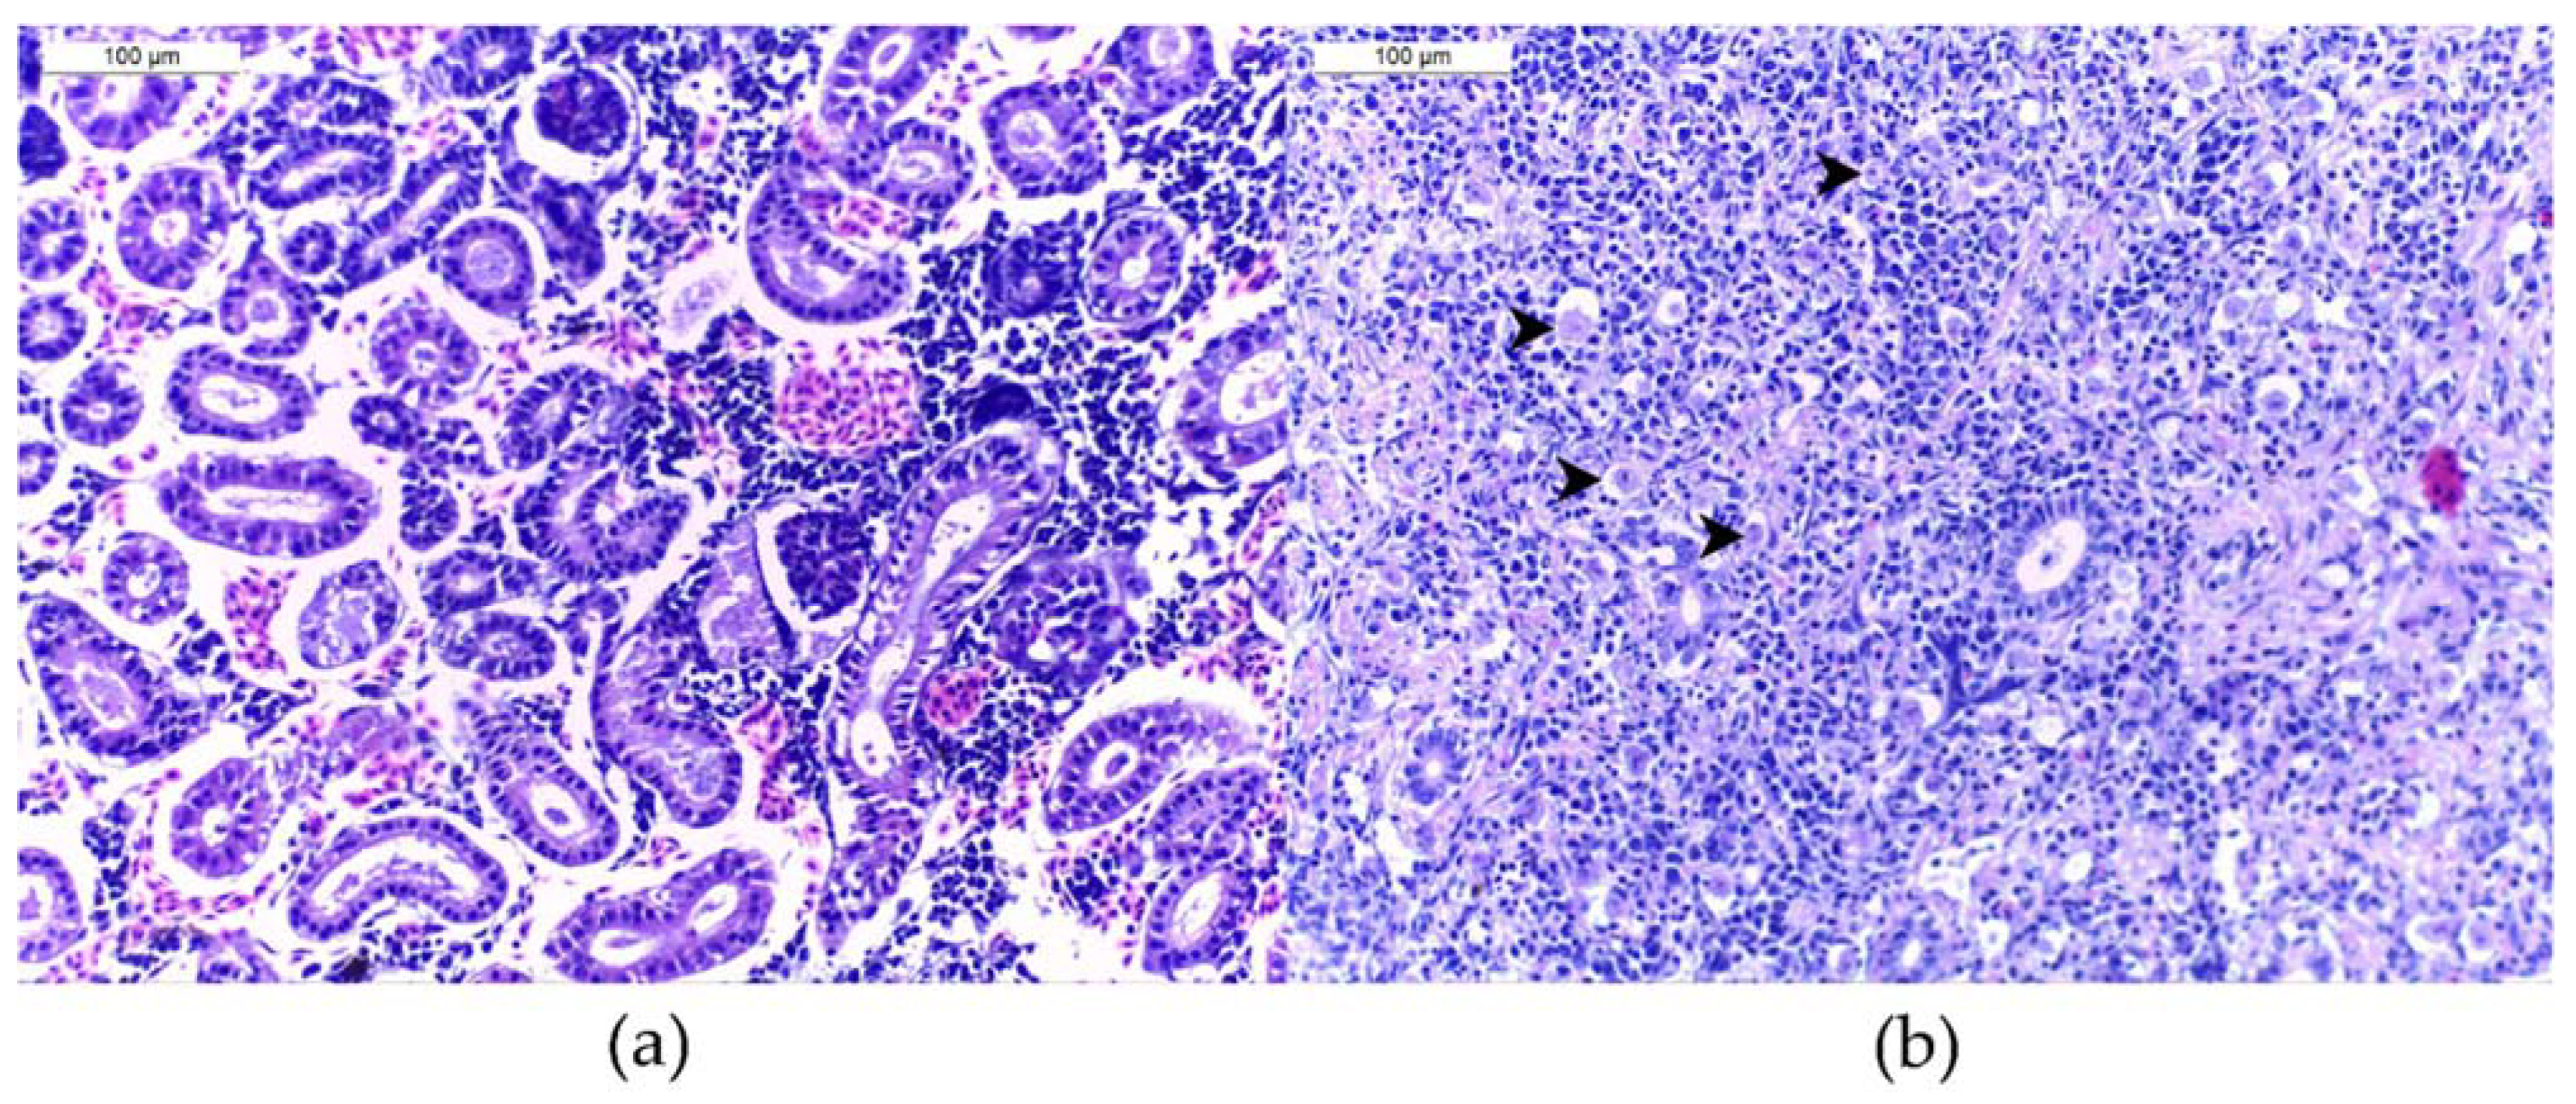

4.2. Histological Analysis